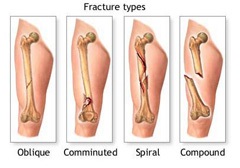

Típusai csonttörések

Szerinti besorolás csonttörések rendkívül változatos. Ez a körülmény annak a ténynek köszönhető, hogy minden esetben a törés egyesíti a számos tényező kísérő felemelkedésének - .. okoz törést, lokalizáció a sérülés jellegét, lágyrész sérülés, stb törések ofszet minden esetben kapcsolódnak egyik vagy másik formája típusú elmozdulása a csont fragmentumok, a természet a törés és egyéb paramétereket.

A leggyakoribb besorolása törések:

- komplex (más elnevezéssel, ék törések amelyben több aprított csont fragmentumok képződnek);

Emellett ott van a következő osztályozás törések:

- zárt törések, amelyre nincs sérülés a külső bőrre;

- nyílt törések, amelyben van egy épségének megsértése a bőr területén a kár és a fertőzés veszélyét.